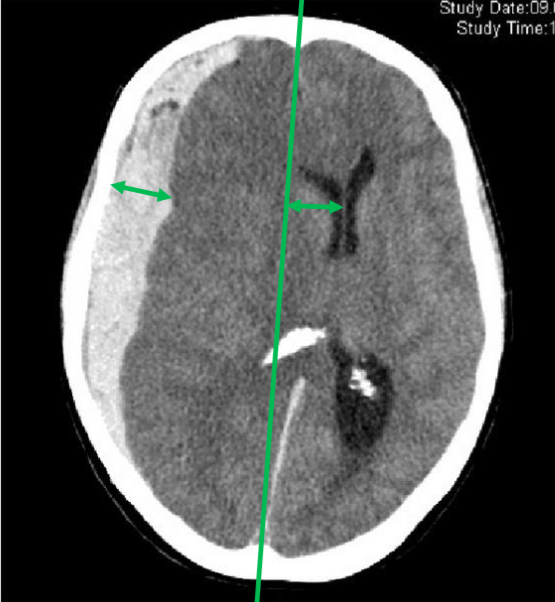

image